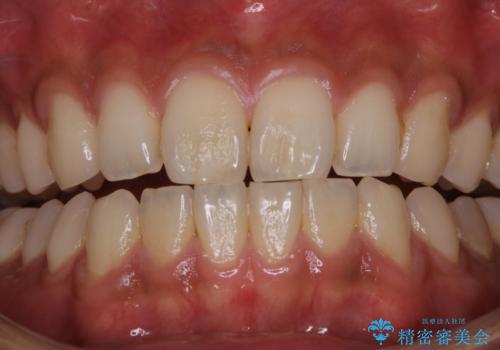

PMTCで清潔感のある明るい口元に

- 歯の色が気になるため、どの処置が適しているか相談してから施術をして欲しいとのことで来院されました。

全体的に汚れが付着していたため、まずはPMTCでご自身の本来の歯の状態にしてから、ホワイトニングにいついて考えましょうとなりました。

PMTCを行うことで、ご自身本来の歯の色になり自然な明るさになります。